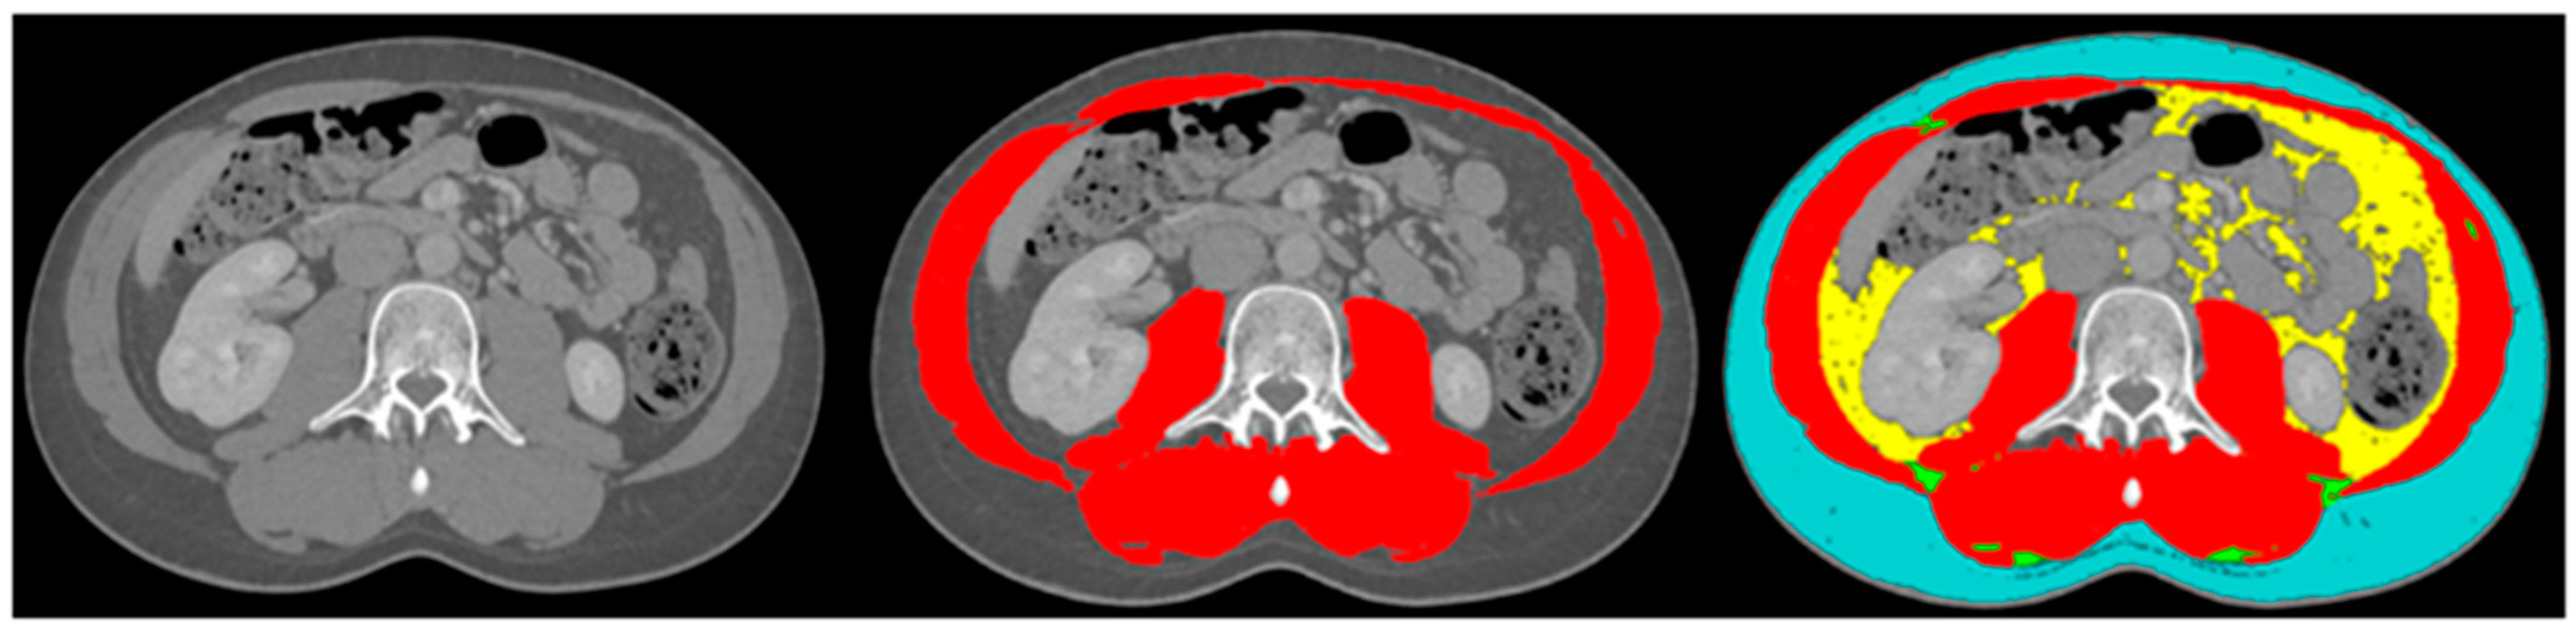

The body composition analysis was performed by two trained researchers (DC and SJ) according to previously published protocols [19,23]. A single slice of the CT scan at the lumbar level L3 was used, as this corresponds with total body muscle and fat mass [24,25]. Slice-O-Matic software (5.0 Rev-8, Tomovision, Milletta, QC, Canada) was used. Relevant tissues were identified based on their anatomical features and tagged with a colour as explained in Figure 1. The software multiplies preset Hounsefield units (HU) with pixels for the tagged area to calculate the relevant areas. The areas of interest, the thresholds and the definitions used are summarised in Table 1. Sarcopenia was present if the skeletal muscle area (SMA) corrected for height2 was below reference values. For myosteatosis as a surrogate marker for muscle quality, the muscle attenuation in Hounsefield units was used; myosteatosis was considered to be present if it was below the reference value. The subcutaneous, visceral and intermuscular adipose tissue areas were added up to calculate the total adipose tissue area. If this area was below the reference value, adipopenia was present.

Figure 1.

Example body composition analyses. Left image: cross-sectional image at lumbar level L3; middle image: tagged muscle mass (red colour); right image: tagged subcutaneous adipose tissue (blue colour), visceral adipose tissue (yellow colour), intermuscular adipose tissue (green colour) and muscle mass (red colour).